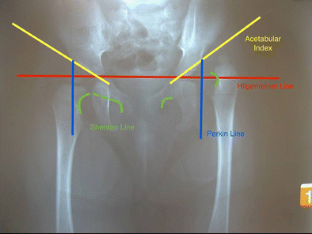

Fig. 1